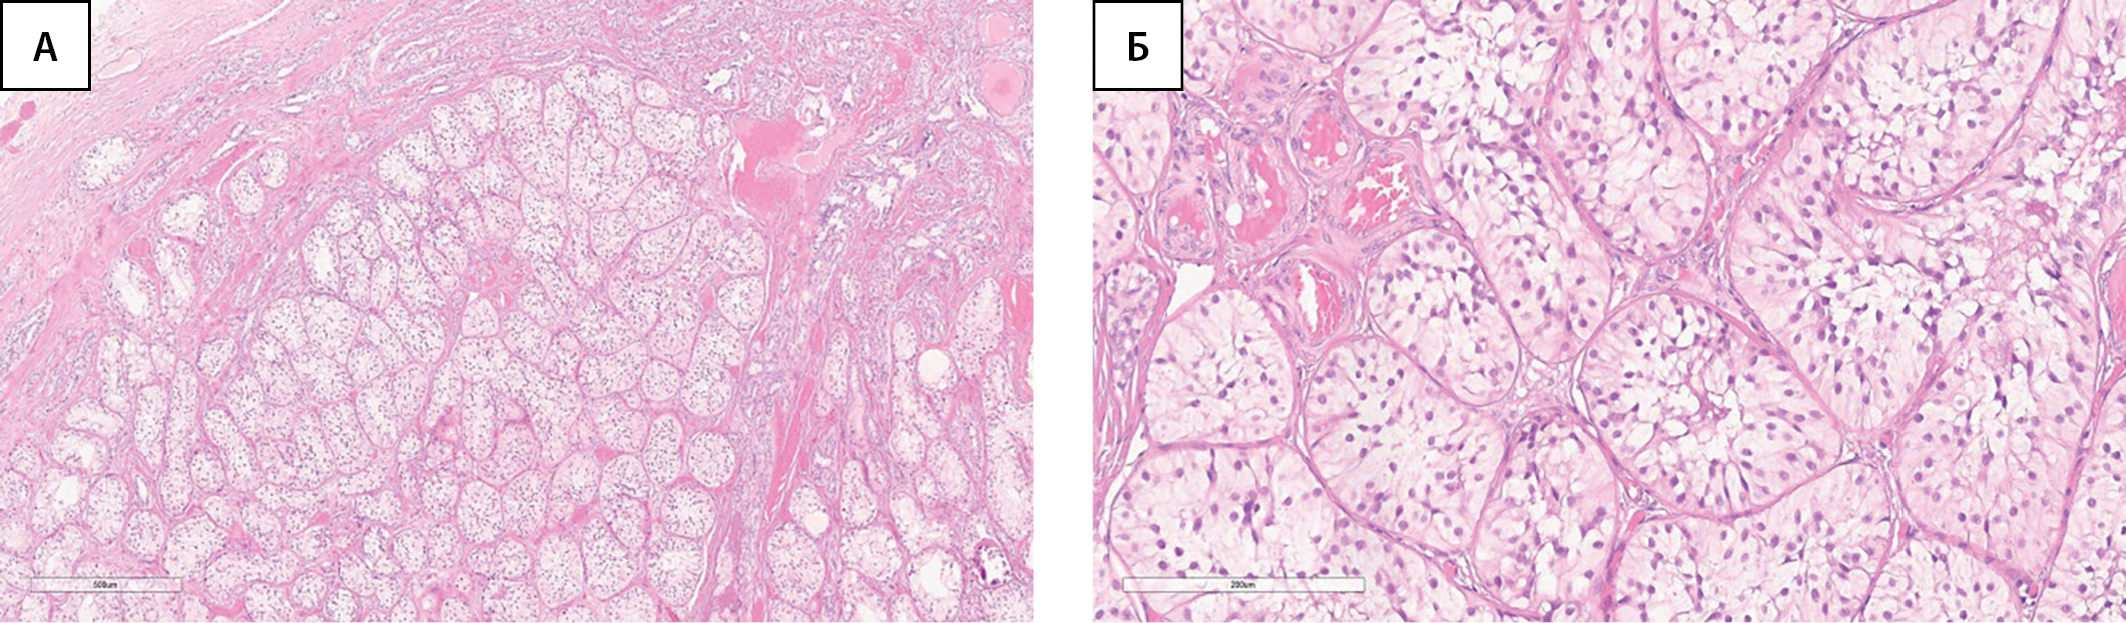

По данным гистологического исследования: гонады с обеих сторон представлены тканью яичка, в которой все трубочки замещены клетками Сертоли, придаток яичка справа обычного строения, в тазовых смывах группы клеток мезотелия (рис. 1).

Рисунок 1. Ткань яичка (без признаков неопластических изменений).

А — окраска гематоксилином и эозином, х40. Б. — окраска гематоксилином и эозином, х200.